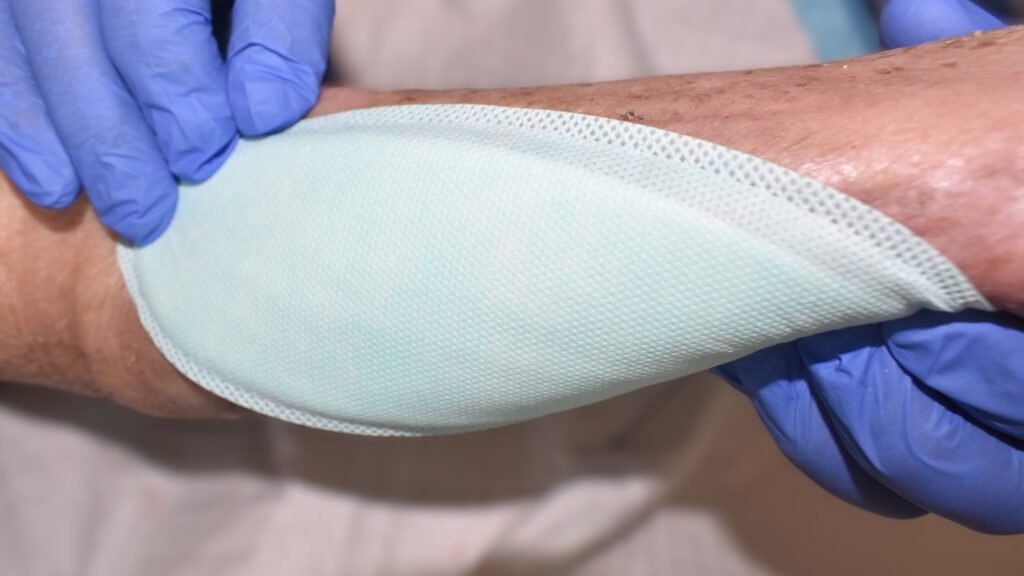

Polyurethan-Schaumverbände -mit Silikonbeschichtung-

Zusätzliche – Fotos ![]() 16 Videos

16 Videos ![]() 4

4![]() Fallbeispiele

Fallbeispiele